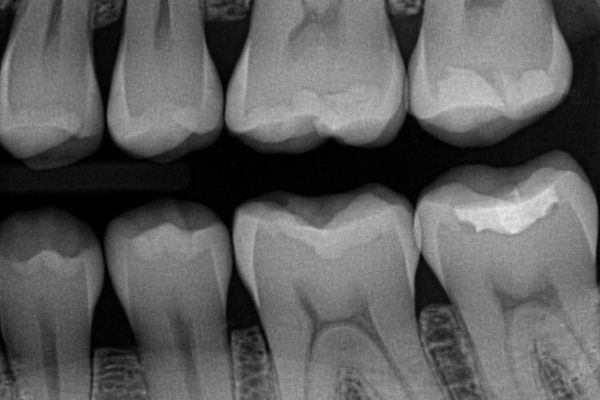

Digital dental x-rays are an essential tool for diagnosing and monitoring your oral health. Instead of traditional film, digital x-rays use an electronic sensor to capture highly detailed images instantly. This allows your dentist to detect cavities, evaluate bone levels, check for infections, and plan treatments with exceptional accuracy — all while keeping your visit quick and comfortable.

- Significantly lower radiation

Digital sensors require far less radiation than film, often reducing exposure by 60–80%. This makes them a safer option for patients of all ages. - Instant, high-resolution images

Because the images appear immediately on-screen, your dentist can review them with you right away. Digital files also provide better clarity and can be enhanced (zoomed, brightened, contrasted) to identify issues earlier. - More comfortable and efficient